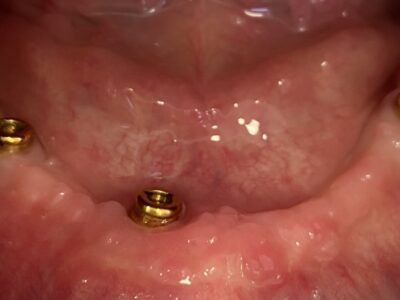

Proteze na implantatima

Proteze na implantatima su idealno rješenje za pacijente koji imaju jaku i zdravu, ali bezubu čeljust. Mogu se postavljati na donje i na gornje čeljusti, a iznimno su zahvalne za higijensko održavanje. Postoje dvije vrste proteza na implantatima: jedne su retinirane (poduprte) prečkama, a druge kuglama (lokatorima). Koja vrsta retencije je adekvatna za pojedinog pacijenta određuje doktor stomatolog, nakon detaljne analize cjelokupne situacije kod svakog pojedinog pacijenta.